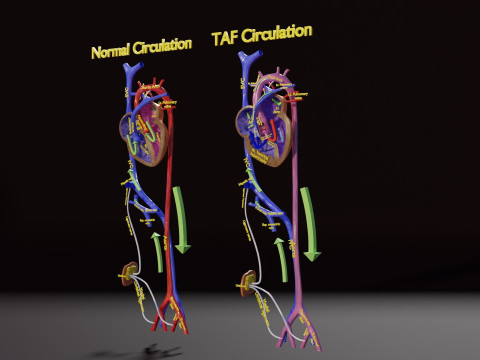

The model meshes include adult circulation versus circulation in Tetralogy of Fallot (TAF), arrow labels and text labels. The blood flow in a patient with Tetralogy of Fallot is outlined in this model. To contrast it to normal blood circulation a separate model of normal circulation is included. The Tetralogy of Fallot (OVER RIDING OF AORTA, PUL STENOSIS, VENTRICULAR SEPTAL DEFECT, RIGHT VENTRICULAR HYPERTROPHY), fossa, ligament teres , venosus, and arteriosus are duly depicted with proper labelling and blood flow directional arrows. Excellent model for teaching, demonstration and knowlegde of human body. The models include both procedural and image textures blend files separately. The texture file include diffuse, roughness and normal png and jpeg based on non overlapping UV maps.